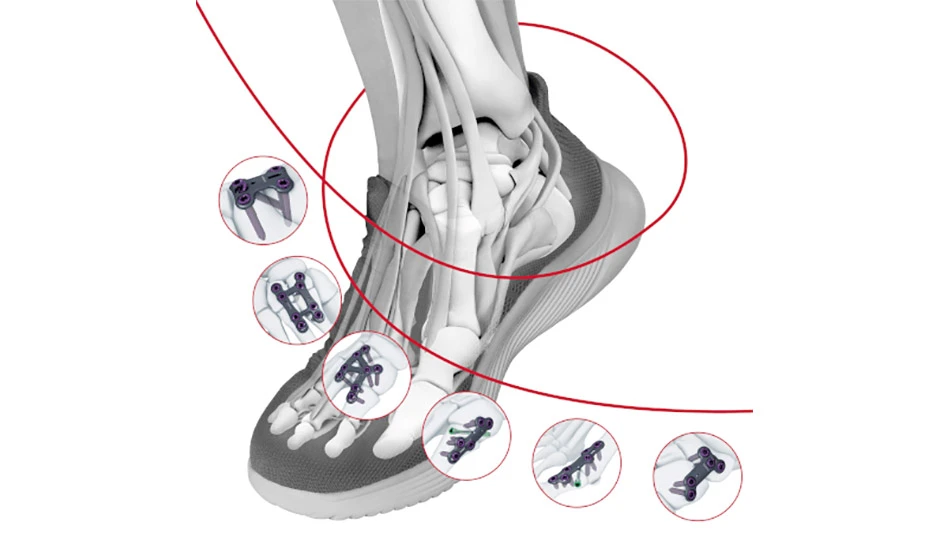

Johnson & Johnson MedTech announced that DePuy Synthes, The Orthopaedics Company of Johnson & Johnson received 510(k) clearance from the U.S. Food and Drug Administration (FDA) for its TriLEAP Lower Extremity Anatomic Plating System, a comprehensive yet modular, procedure-specific system designed to meet the complex needs of orthopaedic surgeons, doctors of podiatric medicine, and foot and ankle specialists. The TriLEAP System provides a diverse offering of contoured and conventional plates that can accommodate multiple screw diameters, and instruments that can be used during the reduction, internal fixation and fusion of bones and bone fragments.

Elective foot surgeries for conditions like bunions are among the fast-growing segments of extremities procedures in orthopaedics and podiatry. In the U.S., one in four people suffer from bunions, or hallux valgus, a progressive disorder of the foot in which deformity gradually increases and can eventually compromise desired lifestyle or mobility. Foot and ankle plating systems are implants that are used for bunionectomies, osteotomies, fusions and fractures of the foot or ankle. The systems are attached by surgeons to the affected area and are designed to stabilize the bones.

The TriLEAP Lower Extremity Anatomic Plating System offers multiple procedure-specific plate options to cover a wide range of procedures, as well as an extensive procedure‐specific implant choice with multiple screw shaft diameters that provide surgeons with various options for intraoperative decisions.

DePuy Synthes expects the TriLEAP Lower Extremity Anatomic Plating System to be available in the U.S. in 2024.